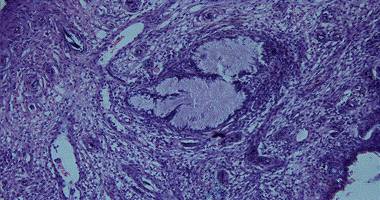

: glandulous cystous hyperplasia is characterized by focal thickness of mucous membrane of cervical canal, glands are covered with prismatic epithelial which produced mucus. Page 4.

4. Glands are covered with prismatic epithelial which produced mucus.

cystic widened glands with dense epithelium and partly swollen dense stroma may be observed.papillary pseudoerosion of uterine neck the formation of papillary outgrowths of cylindrical epithelium with eosinophili are observed. Page 5.